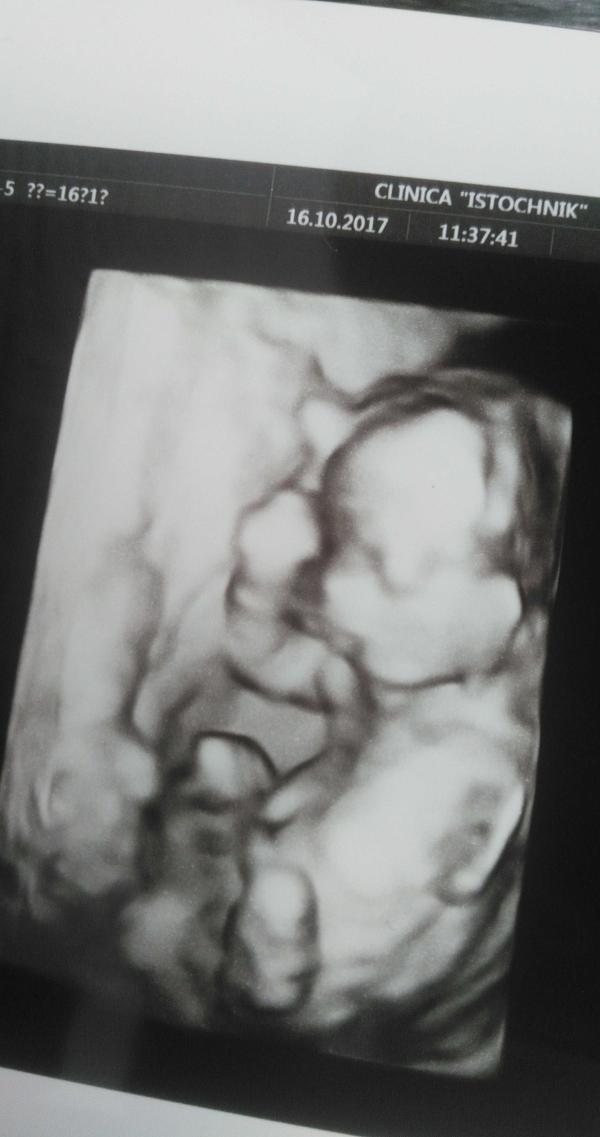

Ну что ж, мальчик у нас, однако 😍😊 На радость всем ❤️

Мамин котёнок 😊

Ездила в "источник" к Мещерякову, капец как там круто, конечно! И врач очень классный! Прям вот советую от души 🙄

@victoriaberm да, просто УЗИ) мне просто не понравилось, как первый скрининг сделали. Подождала немного, чтобы пол заодно узнать и пошла сама. Ко врачу, которого все советуют )))